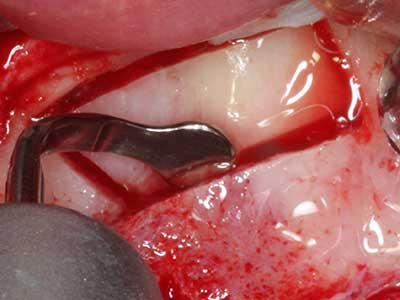

Когато се извършват хирургични процедури върху кост в непосредствена близост до чувствителни структури като кръвоносни съдове или нерви, ротиращите инструменти създават значителен риск за ятрогенно нараняване. Пиезоелектрическите апарати могат да бъдат от помощ при препарация на костно покритие и отстраняване на твърда кост близо до нерви, особено за оголване на нервите след ятрогенно нараняване, както и по време на латерализация на нервите за резекционни и реконструктивни процедури или поставяне на имплант (Фиг. 17-20). Лекият контакт между пиезонакрайника и нерва по принцип не води до нараняване, но ако действате непредпазливо с трионообразни движения или приставки за остатъчен костен субстрат, може да причините временно или перманентно увреждане на нерва. Въпреки това, рискът от увреждане се счита за много по-малък, отколкото при употреба на триони или ротиращи инструменти (Pereira, Gealh et al. 2014).